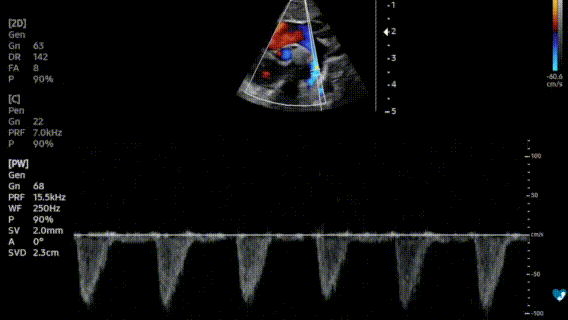

Ecocardiografia pediatrica – Doppler pulsato

• Doppler pulsato e Doppler continuo: consentono di misurare la velocità dei flussi all'interno dei vasi e delle camere cardiache;